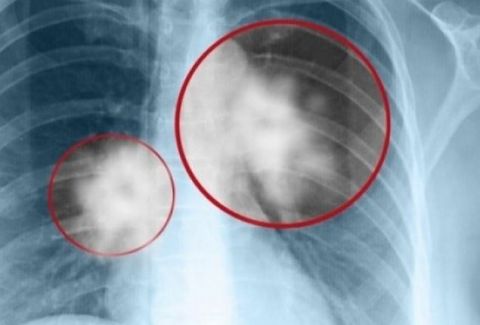

Συνδυασμός φαρμάκων σταματά την εξέλιξη του καρκίνου του πνεύμονα για μεγαλύτερο χρονικό διάστημα

07/10/2024 - 11:20